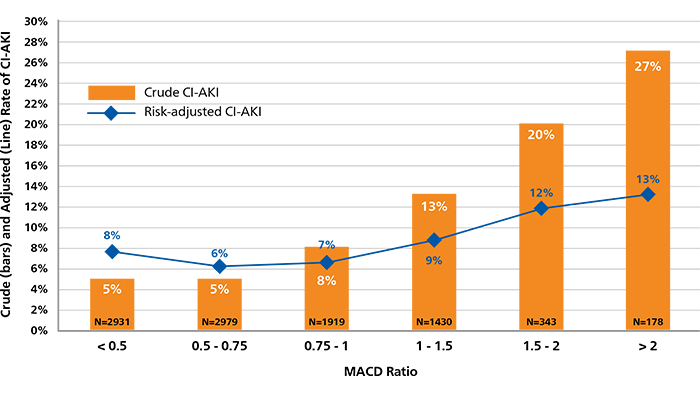

Contrast volume is a key risk factor for CI-AKI and matters the most in the highest-risk patient. The incremental use of contrast beyond the Maximal Allowable Contrast Dose (MACD) is associated with an increased risk of CI-AKI.14

MACD = Contrast volume/eGFR ratio ≤ 1.

MACD Ratio and CI-AKI. Calculated ratios of contrast volume to the predicted Maximal Allowable Contrast Dose (MACD) are plotted by the crude (orange bars) and risk-adjusted (black diamonds) rates of contrast-induced acute kidney injury (CI-AKI).